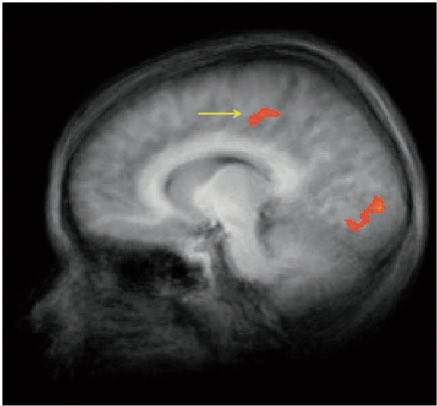

على اليمين عقل الطفل لما يعرض عليه طعام عادي، واليسار لما يعرض عليه نفس الاكل لكن بتغليف ماكدونالدز، اليمين يوضح نشاط في منطقة OFC والمرتبطة بتحديد السلوك وصنع القرار!!